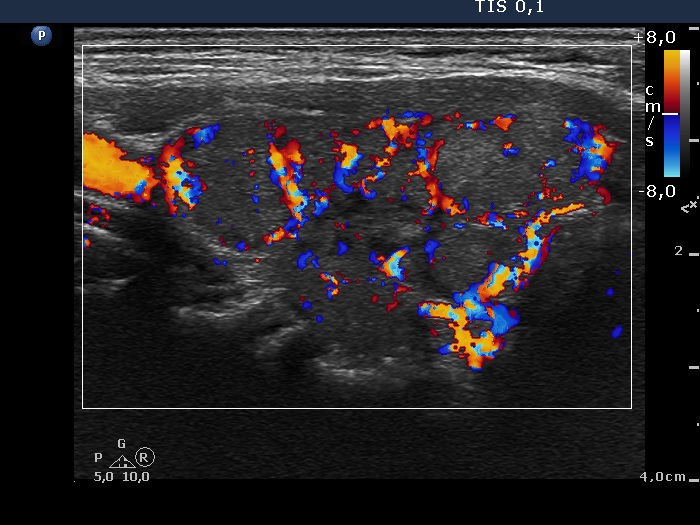

Ultrasonography. The thyroid was echonormal. There were multiple moderately hypoechogenic nodules in the right lobe making the appearance micronodular. There was a relatively larger hyperechogenic nodule in the isthmus. The left lobe contained a hypoechogenic lesion, which presented blurred borders, microcalcifications and an increase intranodular blood flow.